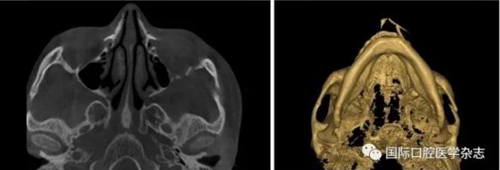

頜面部上下頜骨、顴骨及顴弓骨折、骨折片移位壓迫咀嚼肌群和下頜骨喙突,影響下頜骨的活動(dòng)而造成張口受限[10-12](圖 9、10)。

左:顴弓骨折CT平掃;右:顴弓骨折CT三維成像。

圖 10 顴弓骨折